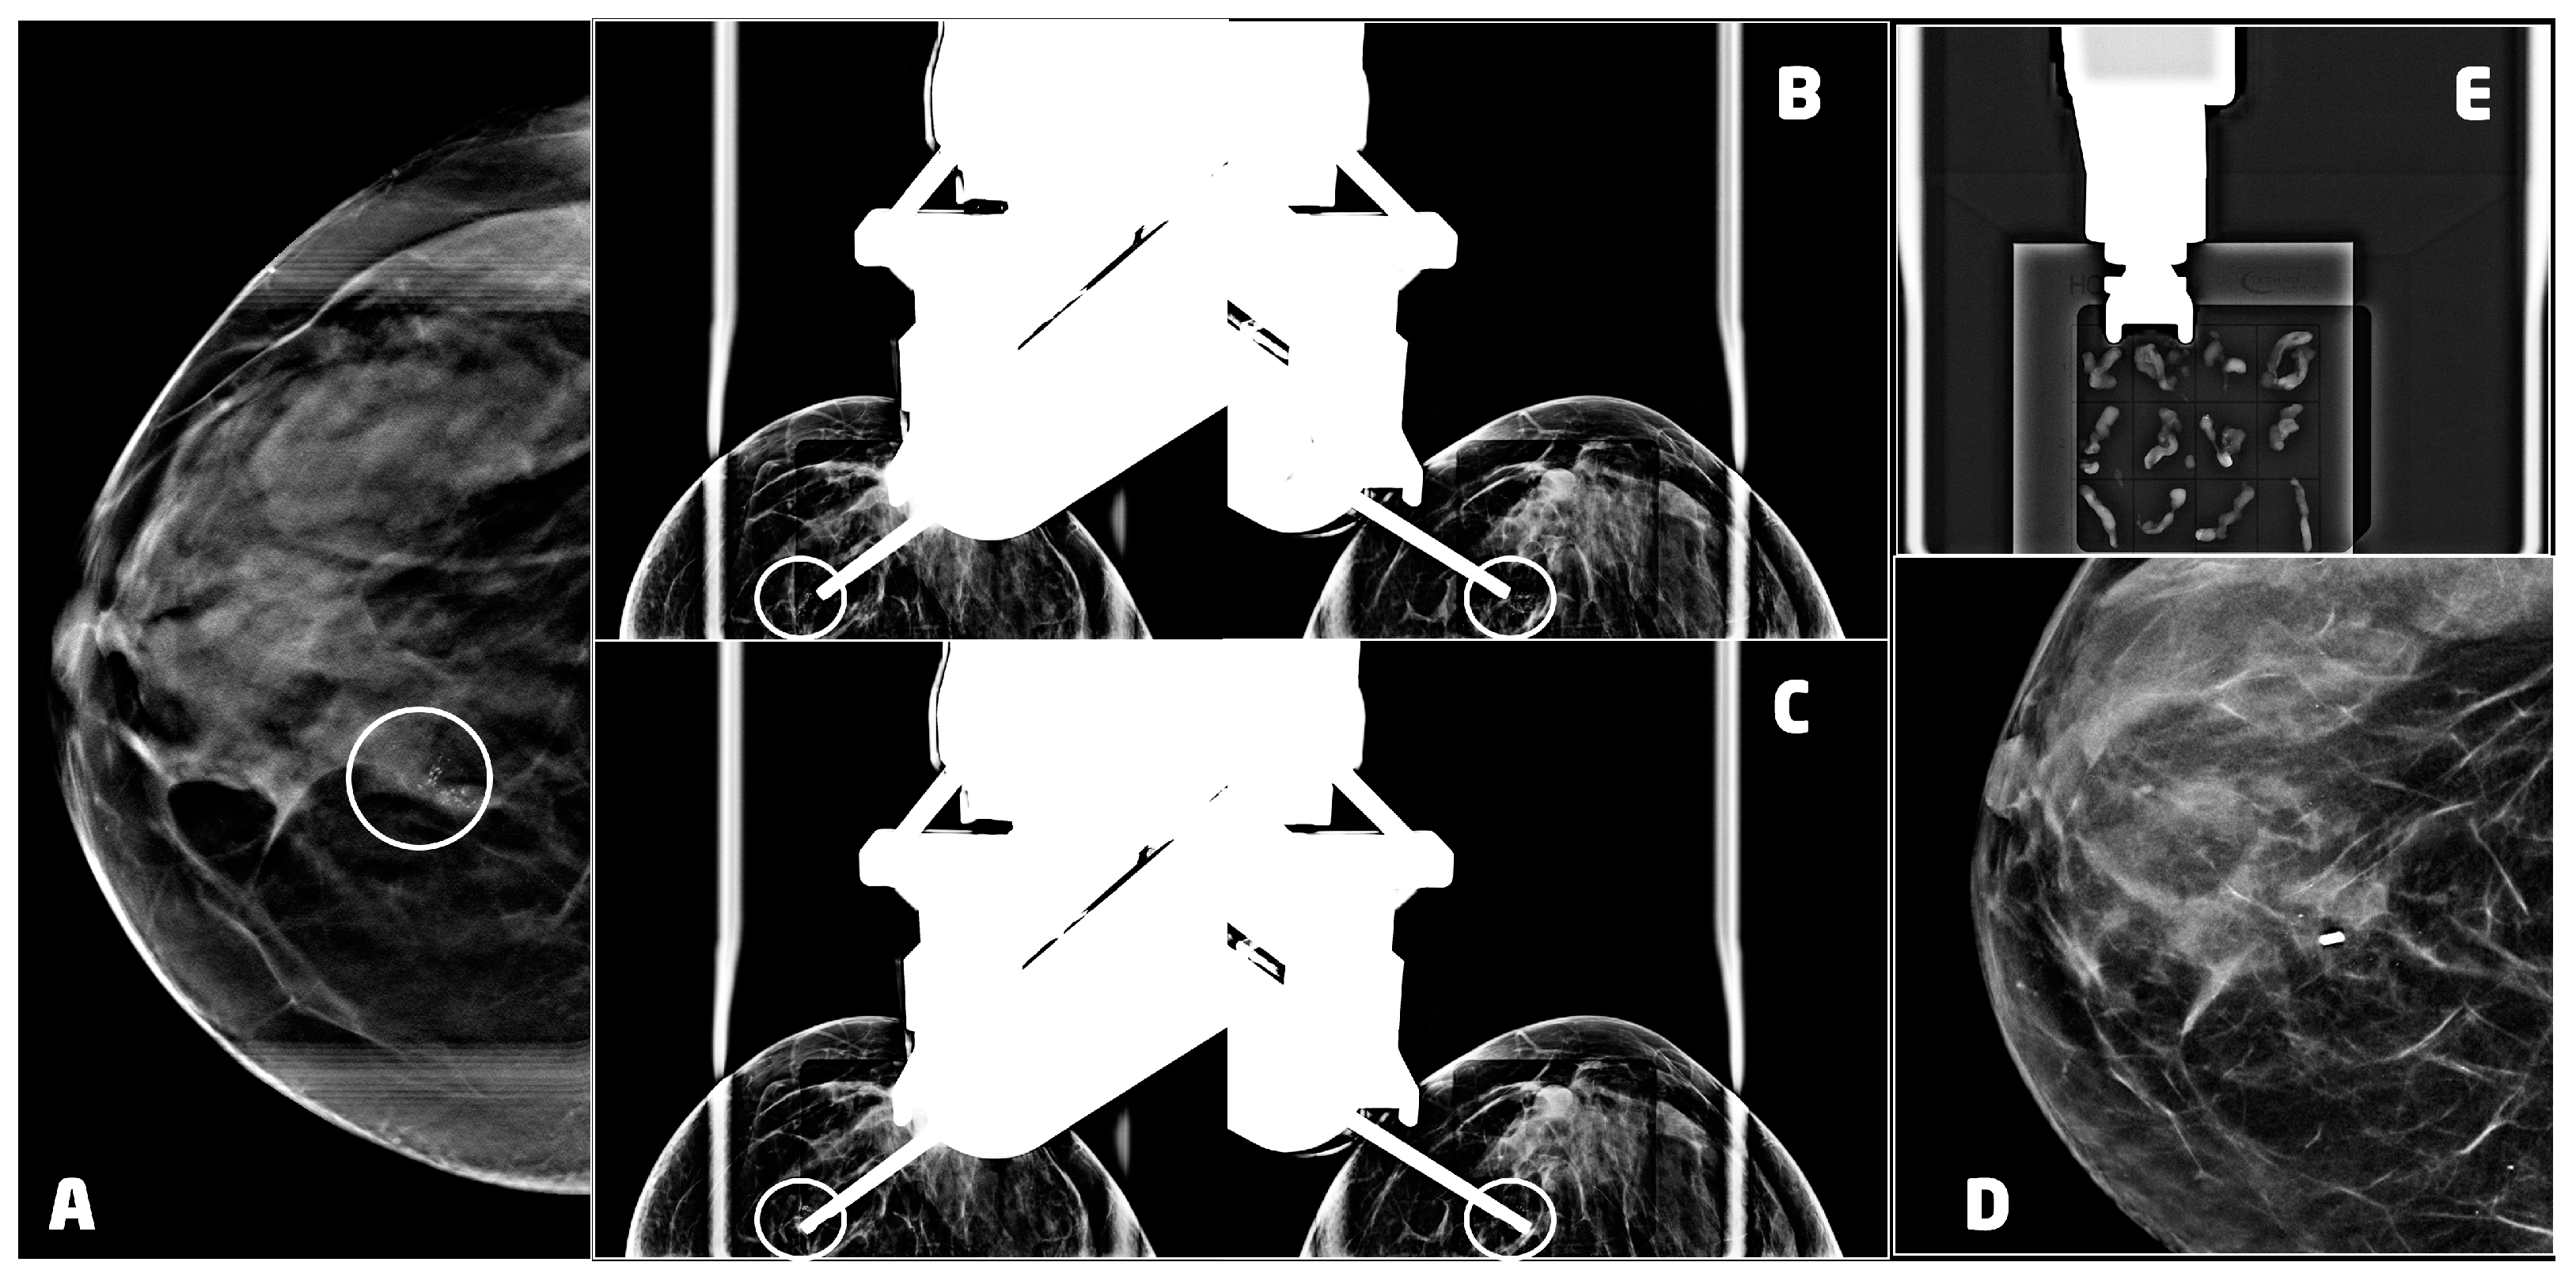

Once the patient is positioned with the best approach chosen in the planning phase and the breast is compressed, we perform the DBT to identify the target lesion (Figure 3A). The choice of the gauge and the aperture of the needle depend on the size, the position of the lesion, and the breast compressed thickness. In our department, we mostly use 9 G or 12 G needles with 20 mm or 12 mm apertures.

After choosing the most appropriate needle, the skin disinfection is performed. Subsequently, we administer local anesthesia. In our experience, this procedure often determines a displacement of the lesion. Thus, we acquired another DBT image to eventually retargeting it. After that, we insert biopsy needle performing the pre-fire stereotactic image with or without post-fire stereotactic images to confirm the expected needle trajectory, according to the calculated coordinates (Figure 3B,C).

A localizing post-biopsy marker clip, usually a 3 mm titanium clip, is then placed at the biopsy site, and the last image is taken to be sure that it has been released. After the needle removal, we proceed to a strong manual compression and bandaging. To evaluate the results of the procedure and the position of the clip, we prefer to perform the two-view mammography a few days after to avoid another compression that could lead to the forming or the worsening of the hematoma (Figure 3D).

When necessary, a specimen radiograph is then obtained at the of the procedure to confirm the presence of calcifications (Figure 3E).

Figure 3. VABB upright procedure for a 53 years old women with a ductal carcinoma in situ, G3 of the right breast: (A) digital breast tomosynthesis of the right breast, in cranio-caudal projection, showing a cluster of microcalcifications at the union of the inner quadrants (circle); (B) pre-fire stereotactic images of the right breast showing the position of the needle near the suspicious lesion (circle); (C) post-fire stereotactic images of the right breast showing the position of the needle inside the suspicious lesion (circle); (D) 2D synthetic view of the right breast 2 days after the procedure, showing the 3mm titanium clip marking the biopsy site with neither residual microcalcifications nor hematoma; (E) specimen radiograph showing microcalcifications in the samples.